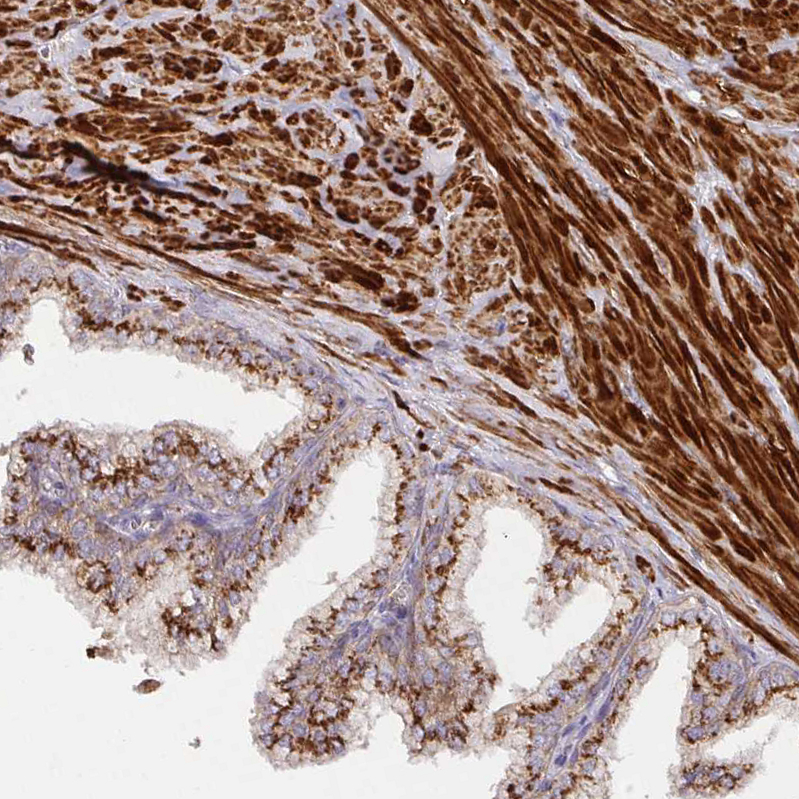

Immunohistochemical staining of human rectum shows strong cytoplasmic granular positivity in glandular cells.